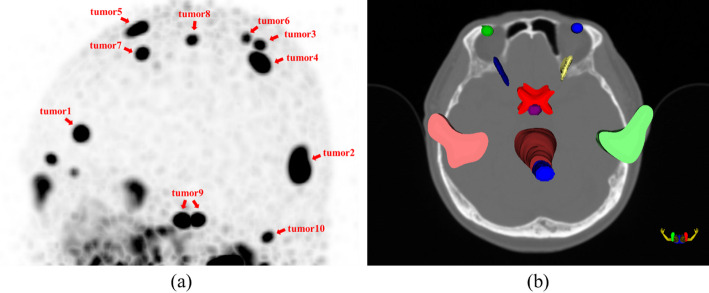

Results: This work establishes an accurate and personalized three-dimensional dose calculation method based on Monte Carlo simulation and multi-modal images of PCa patients with skull metastasis, and analyzes the three-dimensional dose distribution of metastatic lesions and OARs in the brain. Results show that due to the targeting characteristics of 177Lu-PSMA-617, metastatic brain lesions of all patients can receive high radiation doses with the average dose of 0.05 mGy/MBq, and the dose distribution are relatively uniform with the average homogeneity index of 1.23. In addition, the radiation dose received by most OARs are much lower than that of metastatic lesions, but for parotid glands, the dose deposited are only 3.99 times less than that of metastatic lesions due to the high absorption of 177Lu-PSMA-617.